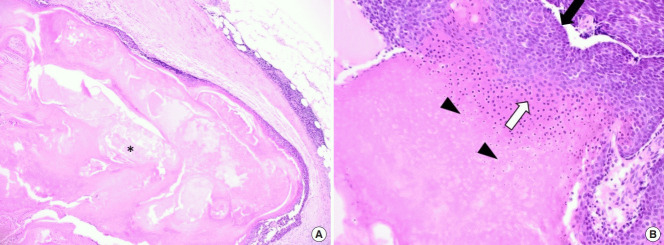

在全身麻醉下,通過皮膚切口有效切除腫塊(圖 4)。 腫塊位于淺表肌肉腱膜系統(tǒng)上方,經(jīng)測量為6.0×5.5×1.5 cm。 組織病理學(xué)檢查根據(jù)特征性發(fā)現(xiàn)診斷為毛母質(zhì)瘤,包括一個有包膜的腫瘤,中心區(qū)域有豐富的嗜酸性無核影細(xì)胞,周圍區(qū)域有藍(lán)色圓形基底樣細(xì)胞。 此外,觀察到多核巨細(xì)胞以及多灶性營養(yǎng)不良性鈣化和局灶性異物反應(yīng)(圖 5)。 患者康復(fù)無并發(fā)癥,隨訪 6 個月未見反復(fù)。

圖 5:顯微檢查顯示毛母質(zhì)瘤的典型特征。 (A) 在皮下組織中發(fā)現(xiàn)結(jié)節(jié)狀包膜腫瘤,中央壞死(星號)和瘤周輕度淋巴細(xì)胞浸潤(H&E,×40)。 (B) 腫瘤由厚纖維包膜下的外基底細(xì)胞和嗜堿性細(xì)胞(黑色箭頭)和中央嗜酸性細(xì)胞(白色箭頭)組成,具有毛母質(zhì)瘤特征的無核影細(xì)胞(箭頭)(H&E,×100)。